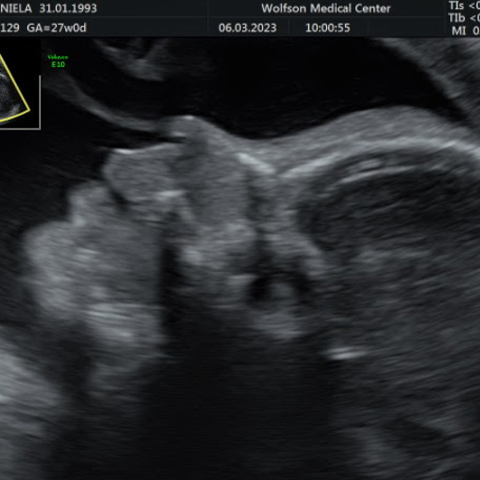

גלריה